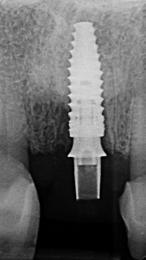

2. ábra: Kezdeti intraorális röntgenfelvétel.

3. ábra: A felső középső metszőfogak kezdeti Cone Beam CT felvétele, jobb felső fogsor első metszőfog (a), bal felső első metszőfog (b).

kális fertőzés a műtét helyén, valamint korábbi GBR/BTR kezelés a fogeltávolítás helyén Betegenként minimum egy egy-gyökerű fog kutatásba való bevétele történt meg (1 ábra) Minden kutatásba bevont beteget két független parodontológus vizsgált meg, hogy megbizonyosodjon arról, az eltávolítandó fogak reménytelen prognózisúak Standardizált intraorális röntgenfelvételek (2. ábra) és CBCT- felvételek (3. a-b ábra) készültek a vizsgálati helyen� A CBCT-felvételeken a keményszöveti- és alveoláris dimenziók preoperatíve megmérésre kerültek Összesen kilenc, reménytelen prognózisú (két független klinikus által igazolt) fog került eltávolításra helyi érzéstelenítésben, 4%-os epinefrin és 1:100000 arányú adrenalin segítségével Az extrakciókat fogó, és szükség esetén emelő kíméletes alkalmazásával végezték� Az extrakciós üregek tisztítása lebeny nélküli megközelítéssel történt Lucas-féle kanalakkal és szikével A bukkális dehiszcencia mértékét és az EDS besorolást közvetlen klinikai mérésekkel, PCP-UNC 15 parodontális szondákkal igazolták Azon betegek kerültek bevonásra a studyba, akik EDS 3-4-es

6. ábra: 6 hónapos posztoperatív CBCT-vizsgálat az implantációt megelőzően, (a) jobb felső kvadráns első metszőfog, (b) bal felső kvadráns első metszőfog.

A műtétet megelőzően és azt követően standardizált, intraorális röntgenfelvételek készültek a vizsgált helyeken A varratszedésre 14 nappal a műtétet követően került sor A lágyszövetek kvalitatív értékelését a műtétet követően 1, 3 és 6 hónap elteltével végezték el (5. ábra) A keményszöveti változások radiológiai vizsgálata céljából, hat hónappal a fogeltávolítást követően, standardizált, intraorális röntgenfelvételeket és CBCT-vizsgálatokat (6. a-b ábra) végeztek az érintett helyeken az újra feltárás és az implantáció előtt Az újra feltárást helyi érzéstelenítésben végezték (7. a. ábra) Az újra képződött keményszövet mennyisége a műtét előtt végzett CBCT-felvételen került kiértékelésre Az implantáció helyén 2,6 mm belső/3,6 mm külső átmérőjű trepánfúróval (7. b ábra), (Komet Dental, Lemgo, Németország) szövettani mintavétel (core-biopszia) történt 10 mm mélységben, az implantátum beültetését megelőzően, a tervezett implantátumpozíció hossztengelyében Ezt követően történt meg az implantátumok behelyezése (ICX, Medentis Medical GmbH, Németország), (8. a-b ábra) a core-biopsziás mintavétel helyére, az implantátumrendszer saját fúróival végzett csontfészek-kialakítás után Ha a behelyezést követően az implantátumnak maradt szabadon menetes felszíne, egyidejűleg GBR-műtét elvégzése is történt autogén csont- és xenogén graftanyagok kombinációjával (cerabone®, botiss, Németország) A kompozit-graftot felszívódó membránnal fedték (Jason®, Botiss, Németország), és titánszegekkel vagy varratokkal rögzítették a csonthártyához

Hat hónappal az implantátum beültetését követően az implantátumokat feltárták, az emergencia-profilt ideiglenes fogpótlással alakították ki (9. a. ábra), majd 1 hónappal később a végleges fogpótlások is behelyezésre kerültek (9. b ábra) Intraorális röntgenfelvételek készítése is történt a végleges restaurátumokról a behelyezésükkor (10. a. ábra), és 12 hónappal később is, mindenfajta csontfelszívódási jel nélkül (10. b ábra)

10. ábra: (a) Intraorális röntgenfelvétel a végleges helyreállítás elkészítésének végén, (b) 12 hónappal az elkészítést követően.

Az 1. sz. táblázatban látható, az alveolus horizontális méretbeli csökkenése bekövetkezett, függetlenül az alveoláris gerinc prezervációjától, a mérsékelt horizontális zsugorodás egyik esetben sem zárta ki az implantátum beültetését Az alveolus horizontális méretbeli csökkenése 20,7% volt az alveolusok legkoronálisabb részén, 15,9% a koronális mérési vonal alatt 2 mm-rel, és 13,1% a koronális mérési vonal alatt 4 mm-rel A horizontális változásokkal ellentétben a vertikális dimenziók nem mutattak térfogatvesztést, inkább a defektusok szuprakresztális telődése következett be A vertikális dimenziók átlagos növekedése 6 hónap után – a kiindulási értékhez képest – 18,3% volt A szuprakresztális ATB-graftrészecskék megmaradtak, és láthatóan kapcsolódtak az újonnan képződött szubkresztális keményszövethez a reentry során végzett megfigyelésnél Mindazonáltal a szubkresztális területhez képest gyengébb szerkezeti integritás volt megfigyelhető A klinikus szemszögéből nézve, az ATB-grafttal prezervált területek konzisztenciája az implantátum csontfészkének készítése során közel állt a D3-D4 csonthoz A vékony biotipusú esetekben az implantátum feltárását követően, enyhe, kezdeti negatív remodellinget figyeltek meg� (10. a. ábra) A kresztális csont stabilitása a biológiai szélesség kialakulása után is megmaradt, amelyet a 12 hónapos után követéses vizsgálat során a röntgenfelvételek is megerősítettek (10. b. ábra)�